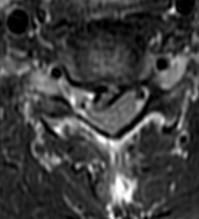

何飞平主任医师团队详细问诊查体,安排相关检查,影像学检查提示:颈C5/C6椎间盘脱出,压迫神经根。与患者及家属沟通病情后,决定予以行手术治疗。

▲颈椎CT、MRI提示:颈C5/C6椎间盘脱出。